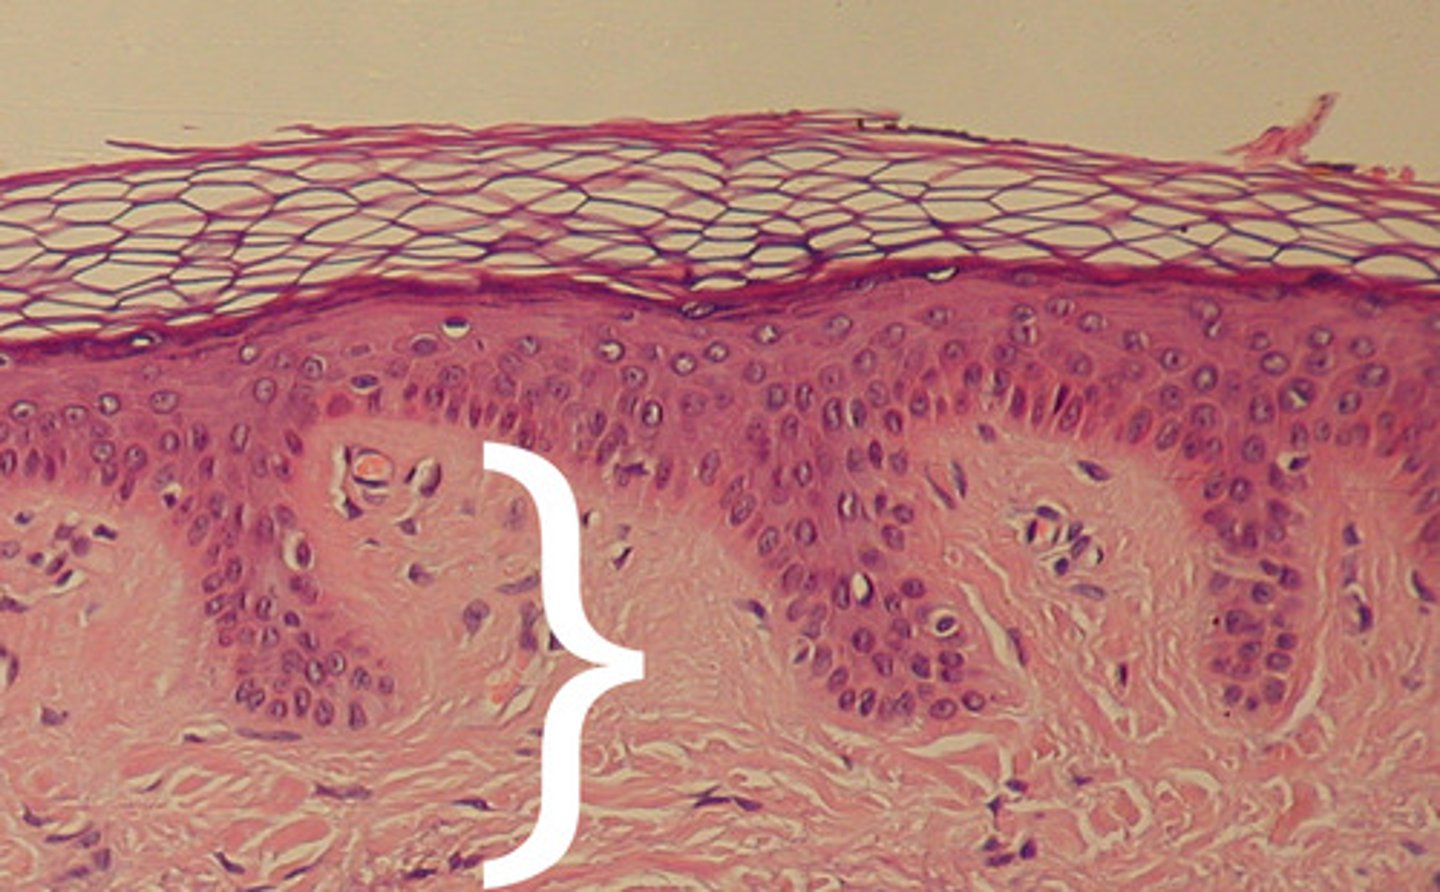

layers of epidermis

Stratum Corneum (Top)

Stratum Granulosum

Stratum Spinosum

Stratum Basale

Stratum Corneum

the most superficial layer of the epidermis consisting of dead cells (flattened keratinocytes with no nuclei)

function: protection for epidermic, physical insults/water loss

granular layer

think layer of keratinocytes

basophilic (blue/purple)

function: keratinization

a layer of the epidermis that provides strength and flexibility to the skin

"prickly" appearance from cell-cell junctions of desmosomes

the deepest layer of the epidermis consisting of stem cells capable of undergoing cell division to form new cells (becomes Stratum spinosum)

cuboidal keratinocytes